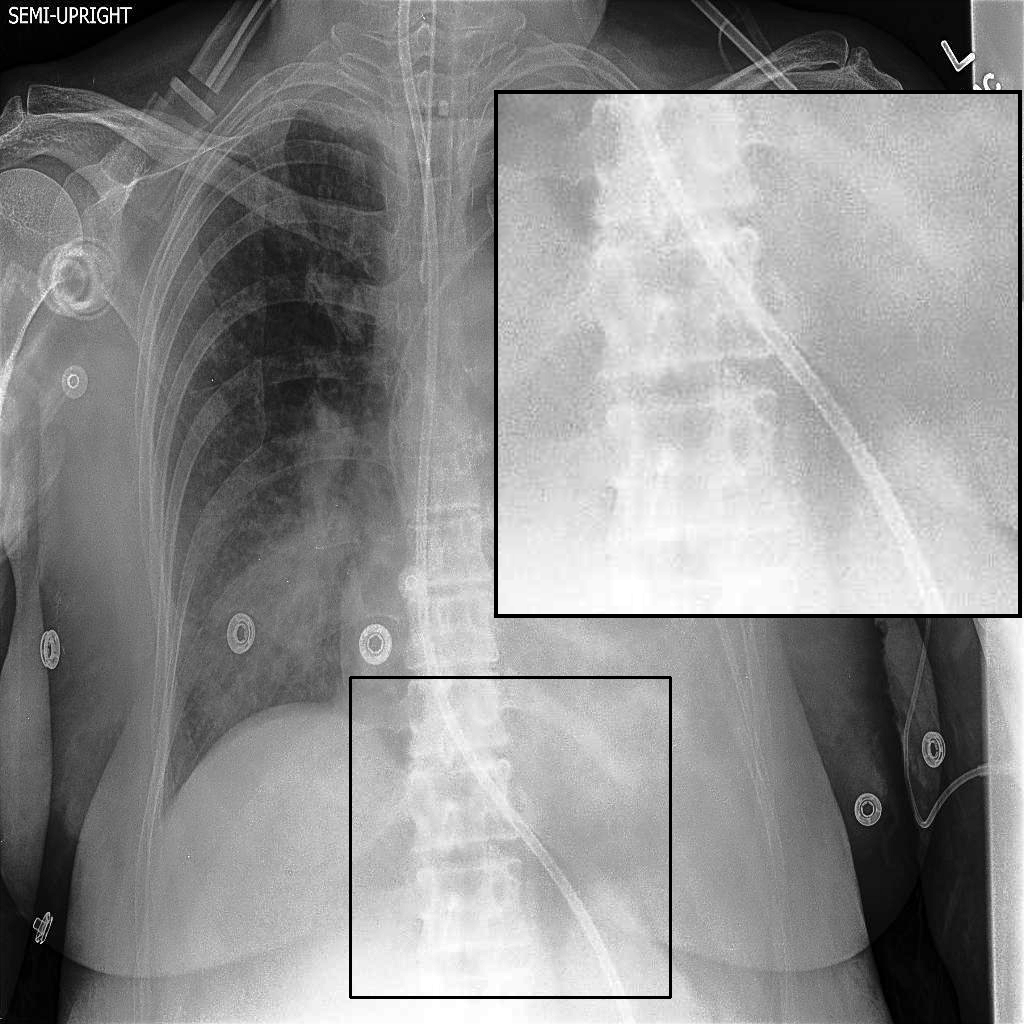

4.2 Training XVertNet

We developed a patch-wise U-Net-based architecture that processes two 512×512512\times 512-pixel regions of interest (ROIs) for each image; one centered on the upper spinal cord and another on the lower spinal cord. As shown in Fig. 3, our datasets exhibit diverse spatial characteristics, with images varying in dimensions (e.g., 2048×20482048\times 2048, 4020×48924020\times 4892, and 1024×10241024\times 1024 pixels) and bit depths (8-bit and 12-bit). This variability in image features poses a significant challenge for creating a robust enhancement model.

Figure 4: Visual examples of different image enhancement methods across datasets; first and second columns present results from the JSRT and Montgomery County Chest X-ray datasets, respectively, while third and fourth columns show results from the NIH Chest X-ray and CheXpert datasets

4.5 A Visual Assessment

Fig. 4 presents representative visual examples demonstrating the superiority of our method in enhancing vertebral contrast compared to several traditional and learning-based image enhancement techniques. The first and second columns show results from the JSRT and Montgomery County Chest X-ray datasets, while the third and fourth columns display results from the NIH ChestX-ray14 and CheXpert datasets. Across all datasets, the highlighted regions of interest (ROIs) emphasize the spinal areas, where fine structures and subtle details are critical for diagnostic assessment. Our method, XVertNet, consistently reveals clearer and more distinct spinal structures without introducing notable artifacts, preserving both global and local anatomical information. In contrast, traditional methods such as CLAHE [7] and Farbman et al. [19] often fail to enhance these subtle features effectively, either producing over-smoothed results or excessively sharpening noise. Similarly, learning-based methods such as ZSSR [43] and Madmad et al. [68] exhibit difficulties in generalizing across different datasets, leading to either insufficient enhancement or visible artifacts. Zero-DCE [33], although effective for natural images, struggles to adapt to the uniform and low-contrast nature of medical X-rays and was not able to supply clear enough contrast-enhanced vertebral structures.

These visual comparisons underline the clinical relevance of our approach. XVertNet successfully enhances diagnostically important structures, particularly in challenging anatomical regions like the spine, where competing methods either distort the features or fail to sufficiently reveal them. This highlights the value of integrating targeted enhancement strategies that are specifically tailored to the unique characteristics of medical imaging data.